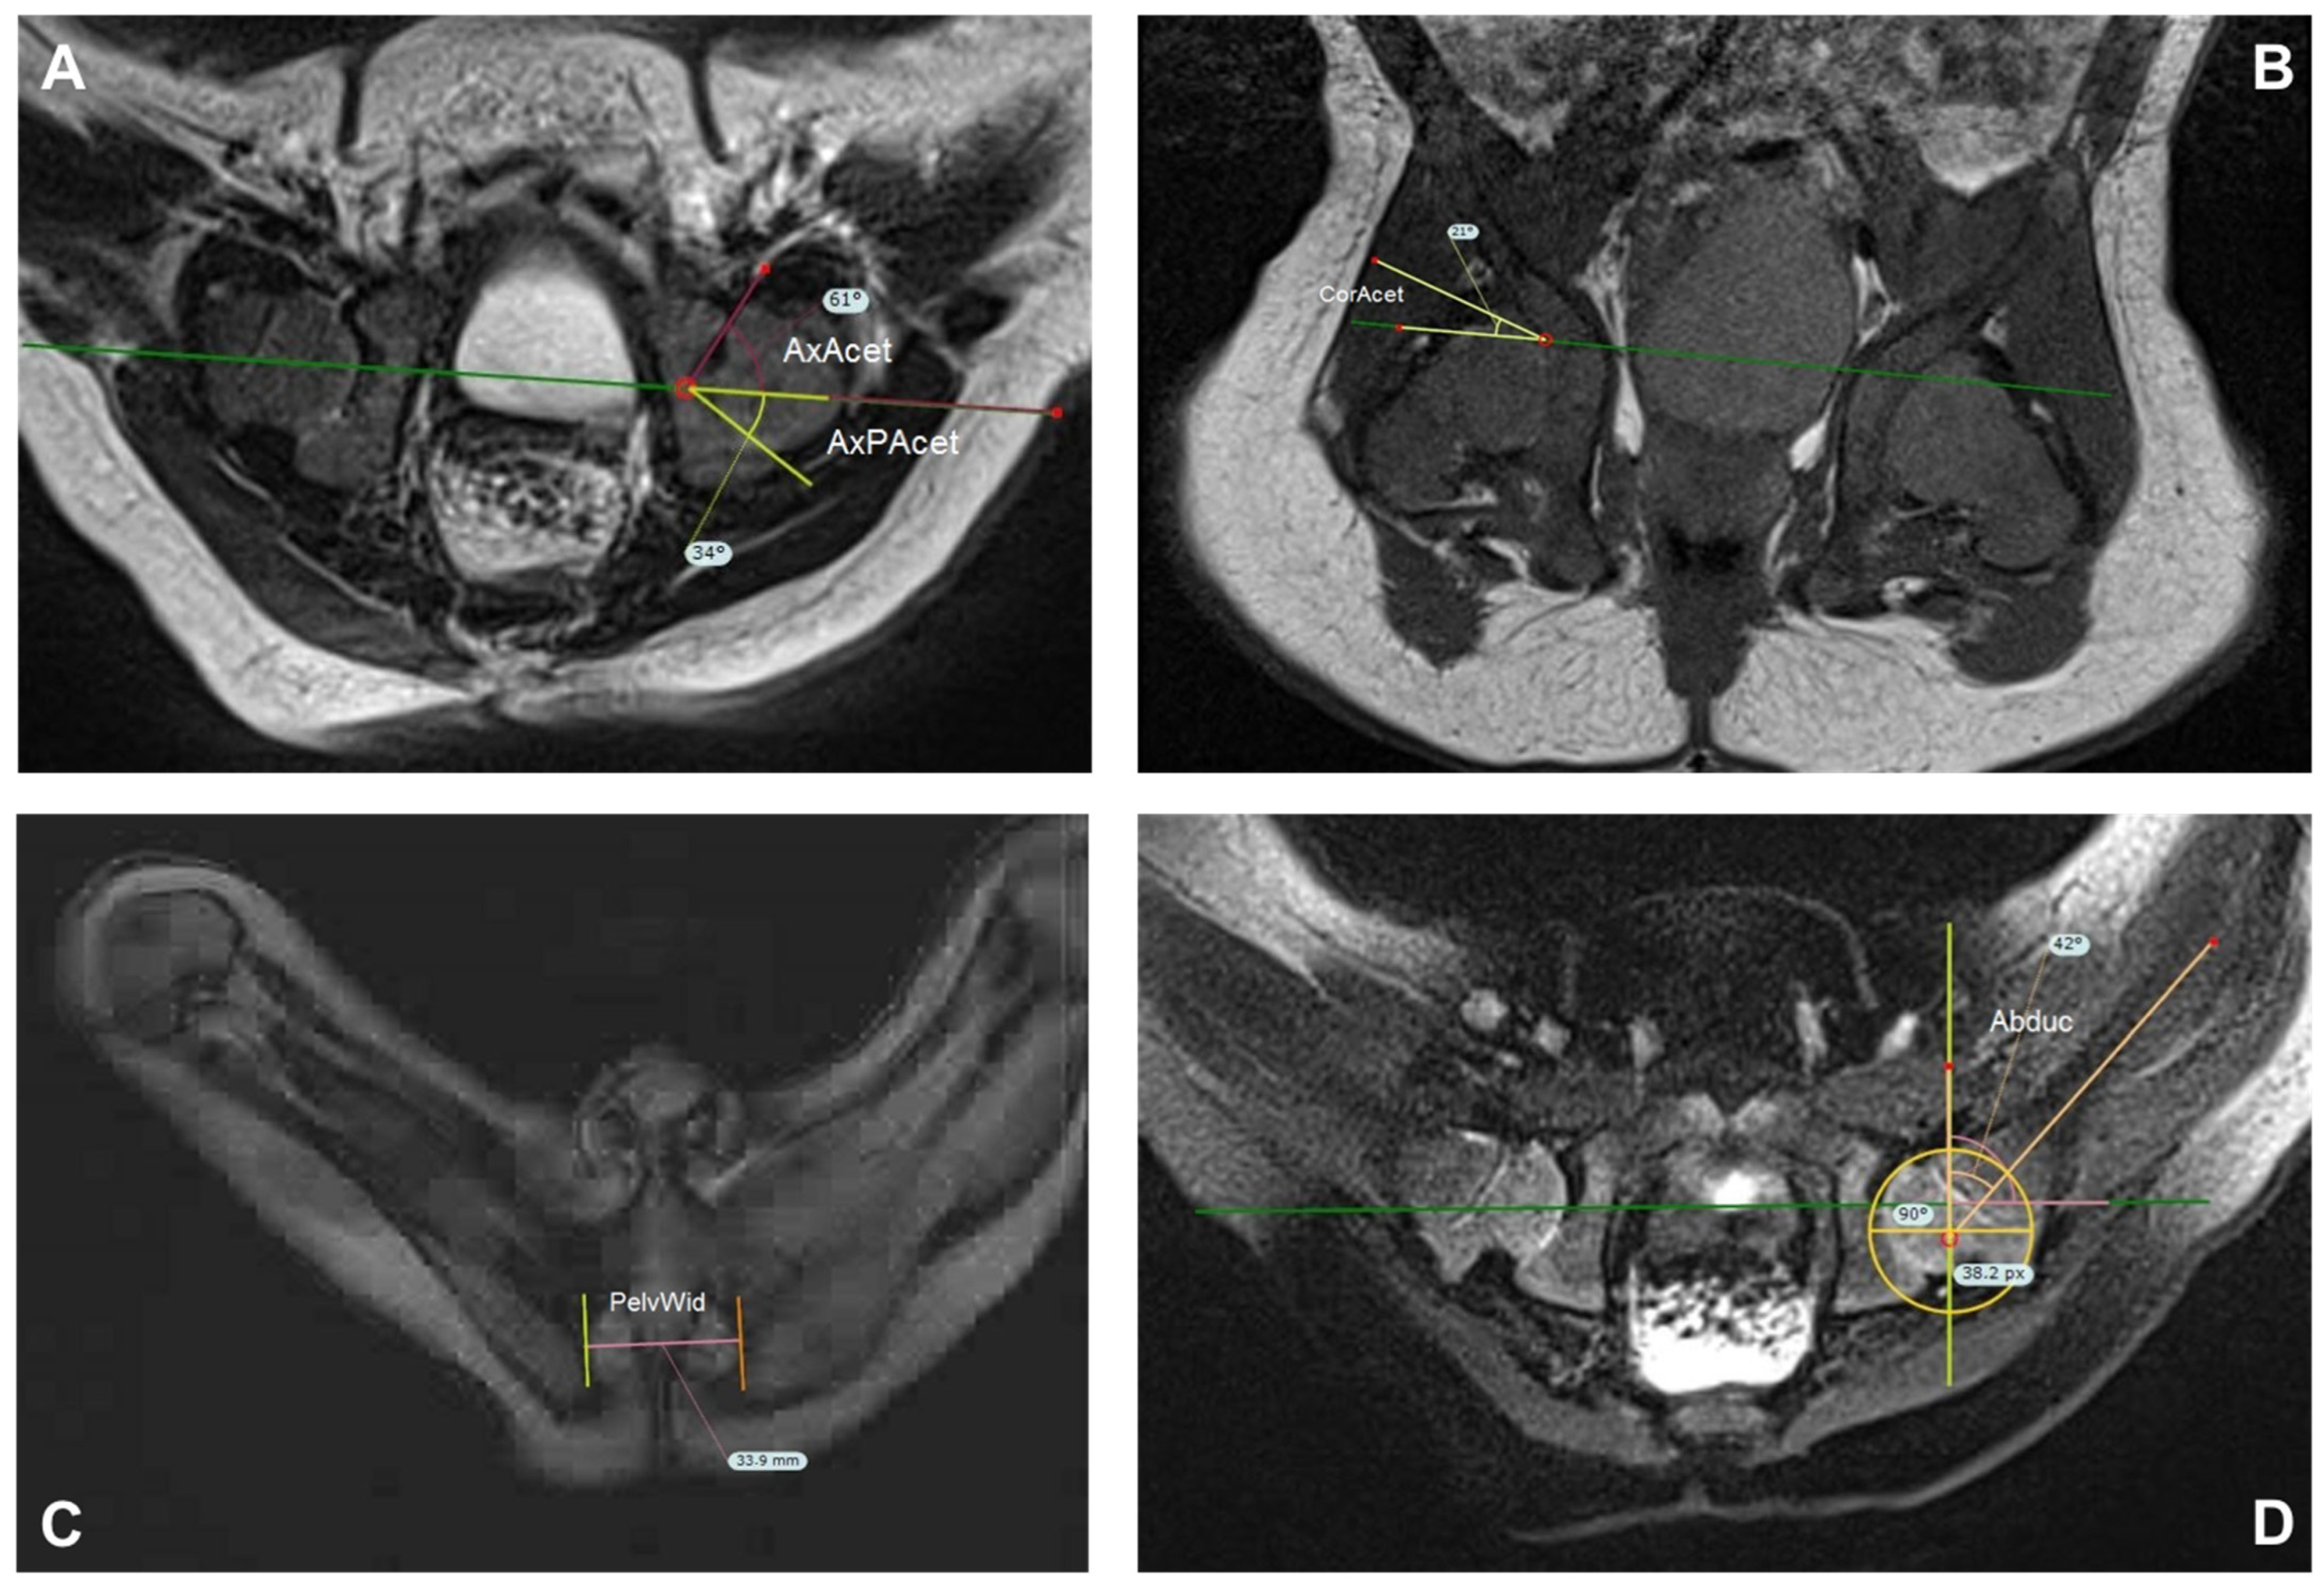

For MRI indices, we used those described by Jaremko et al. (see Figure 4) [26]. First the hip abduction angle (Abd.) is measured in the axial T1 phase on the image with the largest diameter of the femoral heads. This is defined as the angle between a perpendicular line to Hilgenreiner’s line and the line along the mid femoral shaft. The coronal acetabular angle (CorAcet) is measured on the coronal image on which the acetabular roof is steepest. This image must also contain a substantial portion of the femoral head. CorAcet is defined as the angle between Hilgenreiner’s line and a line to the superior bony edge of the acetabulum. For the Pelvic width (PelvWid), we used the image showing the widest distance between medial ischial walls at the pelvic inlet. The width is a measure of the inner distance between the inner edge of left and right cortex. Similarly Jaremko et al., we used the axial image on which the acetabulum appears deepest to measure the anterior and posterior bony axial acetabular angles (AxAcet and AxPAcet). This image also contained a substantial part of the femoral head. The AxAcet is the angle between Hilgenreiner’s line and a line joining the anterior edge of the bony acetabulum to the lateral edge of the triradiate cartilage. The AxPAcet is measured similarly at the posterior joint line [26].

Figure 4.

Overview of the measurement technic in the MRI described by Jaremko and performed in TraumaCad. (A) AxAcet/AxPAcet: Select the axial image for which the acetabular cup appears deepest. The bony anterior acetabulum index (red) is the angle is made between Hilgenreiner’s line (green) and a line joining the anterior edge of the bony acetabulum to the lateral edge of the triradiate cartilage. The bony posterior acetabular index (yellow) is measured similarly at the posterior joint line. (B) CorAcet: Select Slice were the acetabular roof is steepest. Angle (yellow) between Hilgenreiner‘s line (green) and a line joining the superior edge of the bony acetabulum to the lateral edge of the triradiate cartilage. (C) PelvWid: widest distance between medial ischial walls at the pelvic inlet, below the hip joints (D) Abduc: On the slice showing the largest diameter of the most normally positioned femoral bead, draw Hilgenrainer’s line (green) between anterior lateral edges of triradiate cartilage in the same fashion as on the coronal images. Abduc angle (orange) is the angle between the line along the mid femoral shaft and a perpendicular to Hilgenreiner’s line. (AxAcet AxPAcet = anterior/posterior bony axial acetabular angles, CorAcet = coronal acetabular angle, PelvWid = Pelvic width, Abduc = hip abduction angle) [26].